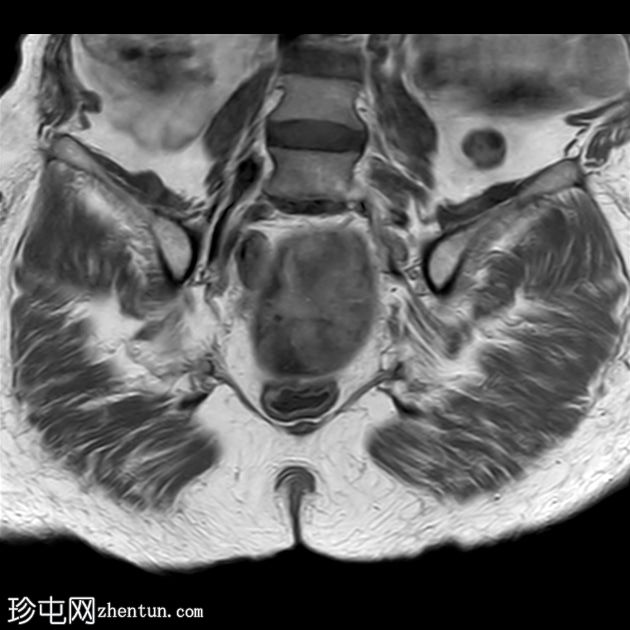

冠状位

T2

3.jpg

子宫呈U形,宫底轮廓消失,宫底突出至扩张的阴道内,宫颈位于内翻的宫底上方(II级子宫内翻):

宫底处可见阴道内可见边界不清、分叶状实性肿块,明显扩张阴道壁,阴道壁完整。

肿块最大轴向及头尾径约为 9.7 x 9.6 x 9.5 cm,T1 加权像呈低信号,T2 加权像呈中/高信号,伴有扩散受限和不均匀增强。

肿块压迫左侧远端输尿管,导致轻度输尿管肾积水。

左侧附件复合体病变,包含实性和囊性成分,轴向径约为 5.3 x 4.7 cm。实性成分 T1 加权像呈低信号,T2 加权像呈中信号,伴有扩散受限和增强。